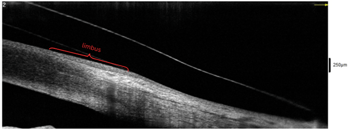

Case Study: Scleral Lens Simplicity: Utilizing Anterior Segment OCT for Scleral Lens Fitting

This case study explores the role of anterior segment OCT in fitting a scleral lens for a patient with keratoconus following corneal cross-linking. Despite being limited to one lens due to cost, the patient experienced significant visual improvement. The case underscores how OCT can streamline the fitting process, enhance precision, and support better clinical decisions in specialty contact lens care.